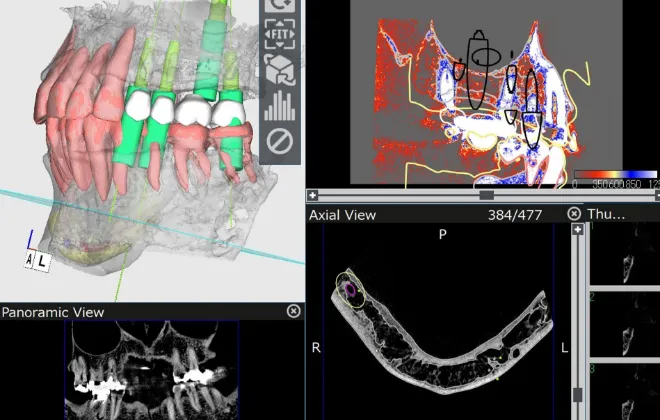

患者様のお口の中を3Dデータ化し

インプラントの埋入位置を正確に分析・診断。

CTスキャンを活用し、

患者様の口腔内を

3Dデータで精密に解析

加藤総合歯科・矯正歯科では、CTスキャンにより口腔内を3D化し、

コンピューターシステム「ビオナ」で歯の状態を詳しく解析します。

専門医とコンピュータ技術が連携し、インプラントの位置や角度をミリ単位で正確に決定、手術時のリスクを最小限に抑えます。